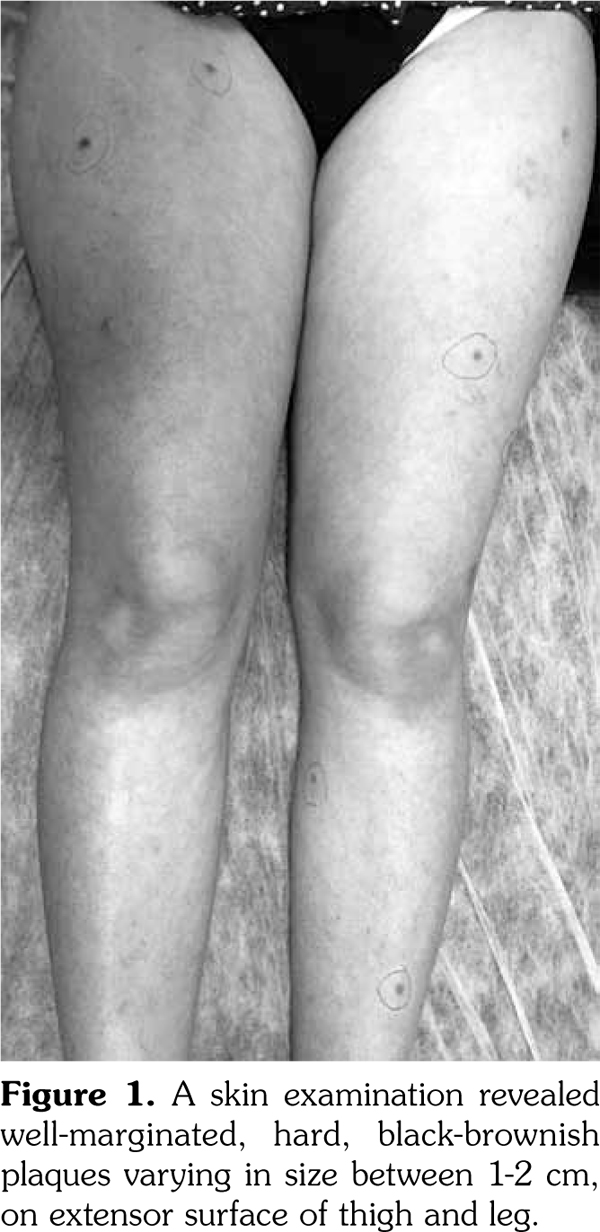

A 37-year-old female patient presented to our clinic with a four-month history of asymptomatic lesions on the torso and in the lower extremities. Patient history revealed that the patient had presented to a hospital five years earlier due to the complaints including photosensitivity, malar rash, oral aft, hair loss, fatigue, and arthralgia and had been diagnosed as having systemic lupus erythematosus (SLE) depending on the clinical signs and symptoms including an erythrocyte sedimentation rate of 83 mm/hour and positive antinuclear antibodies and anti-double stranded deoxyribonucleic acid. Subsequently, the patient had been initiated on methylprednisolone 64 mg/day and hydroxychloroquine sulphate 400 mg/day. For the last five years, the patient had been using systemic methylprednisolone and hydroxychloroquine sulphate at varying dosages. The patient had no history of trauma, injection, or insect bite. A skin examination revealed well- marginated, hard, black-brownish plaques varying in size between 1-2 cm, with three plaques on the anterior torso and six plaques on the extensor surface of the thigh and the leg (Figure 1). Histopathologic examination of a skin biopsy revealed a lesion containing oval fusiform cells and incarcerating collagen fibers was seen in the dermis (Figure 2). Depending on these sign and symptoms, the patient was diagnosed as having multiple eruptive dermatofibromas (MEDFs). No treatment was performed since the lesions resolved spontaneously.